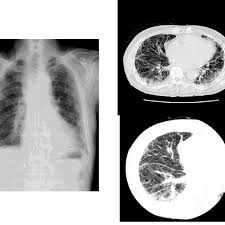

Mesothelioma X Ray Images / Pleural Plaques And Malignant Pleural Mesothelioma In A Patient With Previous Asbestos Exposure Thoracic Key / In general, individuals at risk for and with symptoms of mesothelioma are referred to a specialist in lung diseases, called a pulmonologist.. High resolution is what gives ct its value in the diagnosis of pleural mesothelioma and peritoneal mesothelioma. mesothelioma typically results from exposure to asbestos. The following tests may be performed to accurately stage mesothelioma: The most common mesothelioma finding on radiographs is unilateral, concentric, plaquelike, or nodular pleural thickening (as seen in the images below). A proper mesothelioma diagnosis requires a combination of examinations and an accurate history of potential asbestos exposure.

mesothelioma isn't always fatal and that's the hope to hold on to. images a specialist asbestos removal company removing asbestos from a shed roof of a house in ambleside, cumbria, uk. The most common mesothelioma finding on radiographs is unilateral, concentric, plaquelike, or nodular pleural thickening (as seen in the images below). A proper mesothelioma diagnosis requires a combination of examinations and an accurate history of potential asbestos exposure. A chest radiograph may show pleural effusions or pleural thickening. In general, individuals at risk for and with symptoms of mesothelioma are referred to a specialist in lung diseases, called a pulmonologist. Unusual lumps of tissue under the skin on your chest. mesothelioma patients rely on the information their clinical team obtains from medical imaging. mesothelioma meme,mesothelioma causes,mesothelioma definition,mesothelioma symptoms,mesothelioma prognosis,mesothelioma treatment,mesothelioma what is it,mesothelioma lawsuit,mesothelioma survival rates,mesothelioma law firm,mesothelioma,mesothelioma commercial,mesothelioma cancer,mesothelioma ad,mesothelioma ad script,mesothelioma awareness,mesothelioma applied research foundation. They are a good way to look at bones and can show changes caused by cancer or other medical conditions. Worrisome lesions seen on ct imaging would prompt a biopsy attempt to confirm the diagnosis. Common ones used to diagnose mesothelioma include: These images may show the thickening of the pleural wall, an initial indication of cell malfunction in the pleural membrane.

Sometimes ultrasound images are also used. The different kinds of mesothelioma are based on how the cancer cells look. It's often difficult to diagnose mesothelioma by viewing cells from fluid samples. The most common mesothelioma finding on radiographs is unilateral, concentric, plaquelike, or nodular pleural thickening (as seen in the images below). Pleural effusions are present in 95% of cases and are typically unilateral, large, and hemorrhagic. The problem is that often a ct scan will result in a false positive (in which a biopsy would reveal another condition) or false negative. A computed tomography or ct scan is useful in determining the location, size, and extent of cancer such as mesothelioma. mesothelioma patients rely on the information their clinical team obtains from medical imaging. The following tests may be performed to accurately stage mesothelioma: Check spelling or type a new query. Cxrs are taken to have a look at abnormalities within the lung like thickening of the pleura or nodules within the lungs. They are a good way to look at bones and can show changes caused by cancer or other medical conditions. Maybe you would like to learn more about one of these?.

The most common mesothelioma finding on radiographs is unilateral, concentric, plaquelike, or nodular pleural thickening (as seen in the images below). Pet scans use a dye with radioactive tracers which are typically swallowed or injected into the body. Gm157481749 $ 33.00 istock in stock What does mesothelioma look like on ct scan Malignant mesothelioma is a disease in which malignant (cancer) cells form in the lining of the chest or abdomen. Searches related to mesothelioma chest x ray findings pictures of lungs with mesothelioma mesothelioma images can a chest xray show mesothelioma? More information about imaging tests to diagnose mesothelioma: Pleural mesothelioma, which affects the tissue that surrounds the lungs, causes signs and symptoms that may include: